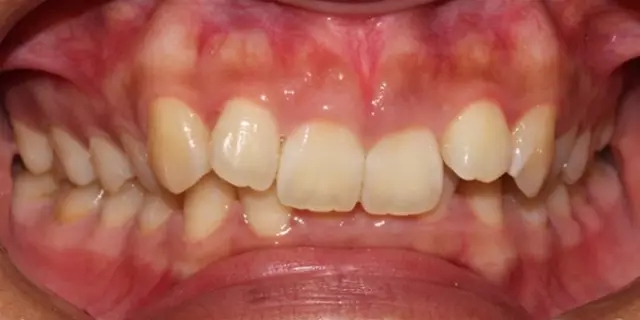

Damon 病例分享:安氏 II 類二分類露齦笑的矯治(董一磊)

治療前后對比